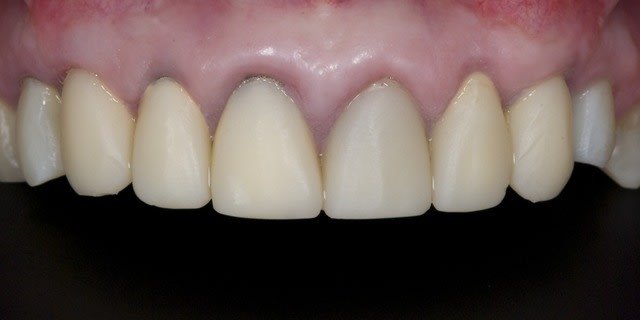

La demande concerne la réhabilitation esthétique du bloc incisif supérieur.

On ne parlera pas de bruxisme, de dvo, de gouttière et de réhabilitation globale pour diverses raisons, seule le traitement esthétique de 14 a 24 nous concerne ici et ses différentes solutions pour le traiter.

Alors j'ai commencé le traitement:

-ext 24 car mobilité type 2 + implant immédiat + couronne prov. en sous occ.

-Démontage difficile des ccm, mais surprise, traitement endo relativement mou et donc a priori pas trop délicat a reprendre.

-couronnes prov.